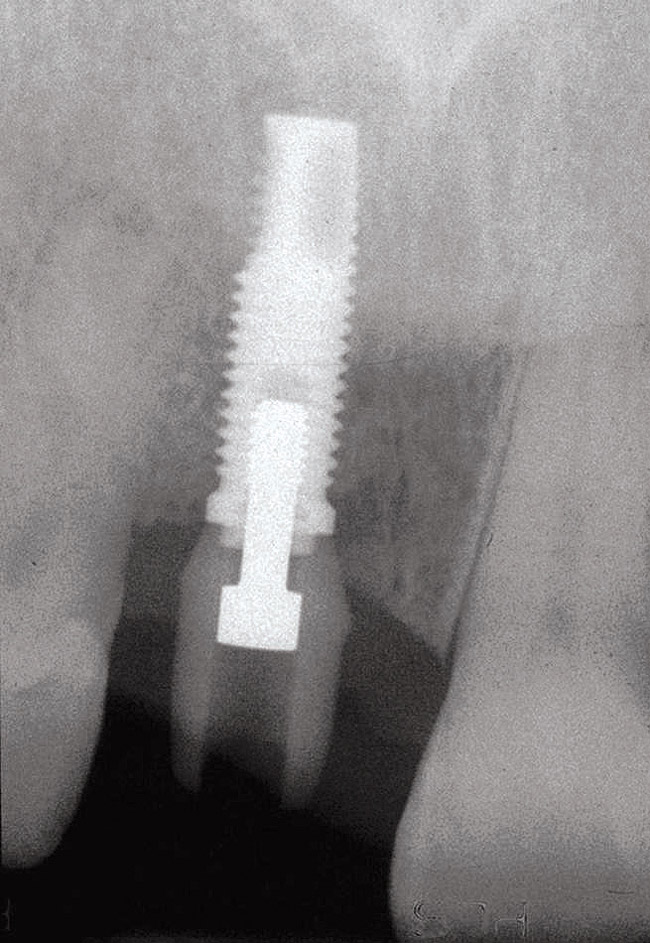

Fig 1. Preoperative radiograph of a case begins a discussion with the patient as to potential treatments, including implant placement, crowns, and crown lengthening, for a better prosthetic result.

Figure 1

Fig 2. After implant placement, the radiograph suggests that without the planned surgical crown lengthening on the adjacent teeth, the implant crown would emerge substantially more apically than the adjacent natural teeth.

Figure 2